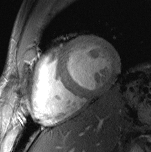

All these efforts culminated in images of the beating heart with a spatial resolution that is by a factor of five superior to that routinely available at 1.5 tesla, and which might come close to turning a 10-megapixel digital camera into a 50-megapixel digital camera. These improvements offer detailed insights into cardiac anatomy and allow accurate delineation of myocardial borders, a feature that is essential for cardiac chamber quantification.

- von Knobelsdorff-Brenkenhoff F, Frauenrath T, Prothmann M, Dieringer MA, Hezel F, Renz W, et al. Cardiac chamber quantification using magnetic resonance imaging at 7 Tesla--a pilot study. Eur Radiol. 2010;20(12):2844-2852.